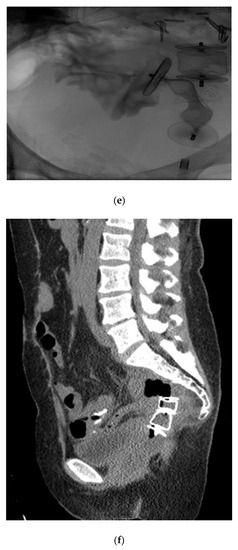

Given the successful short-term outcome, a second patient was referred for the closure of a complex colovaginal fistula resulting from invasive vaginal malignancy and prior surgical intervention. The patient was deemed not to be a candidate for operative repair. The patient had such a significantly poor quality of life that percutaneous closure of the fistula was attempted (Figure 7).

Figure 7.

(a) Sagittal T2 MR shows a large fistula (arrow) between a recurrent mucinous rectal tumor (T) and the vagina (V). The rectum is surgically absent; (b) a guidewire has been passed through the vagina into the fistula with the tumor and colon. Contrast is seen opacifying the cecum and ascending colon; (c) the first Amplatzer device is being deployed; (d) the second Amplatzer device is being deployed; (e) after the Amplatzer device is deployed, contrast is retained in the small bowel and no longer communicates with the vagina; (f) a sagittal CT image shows the two adjacent Amplatzer plugs within the fistula tract.

The patient did well in the short term, having a significant decrease in vaginal output, and an improved quality of life. Furthermore, follow-up imaging demonstrated that the occluder plugs were in the appropriate position.